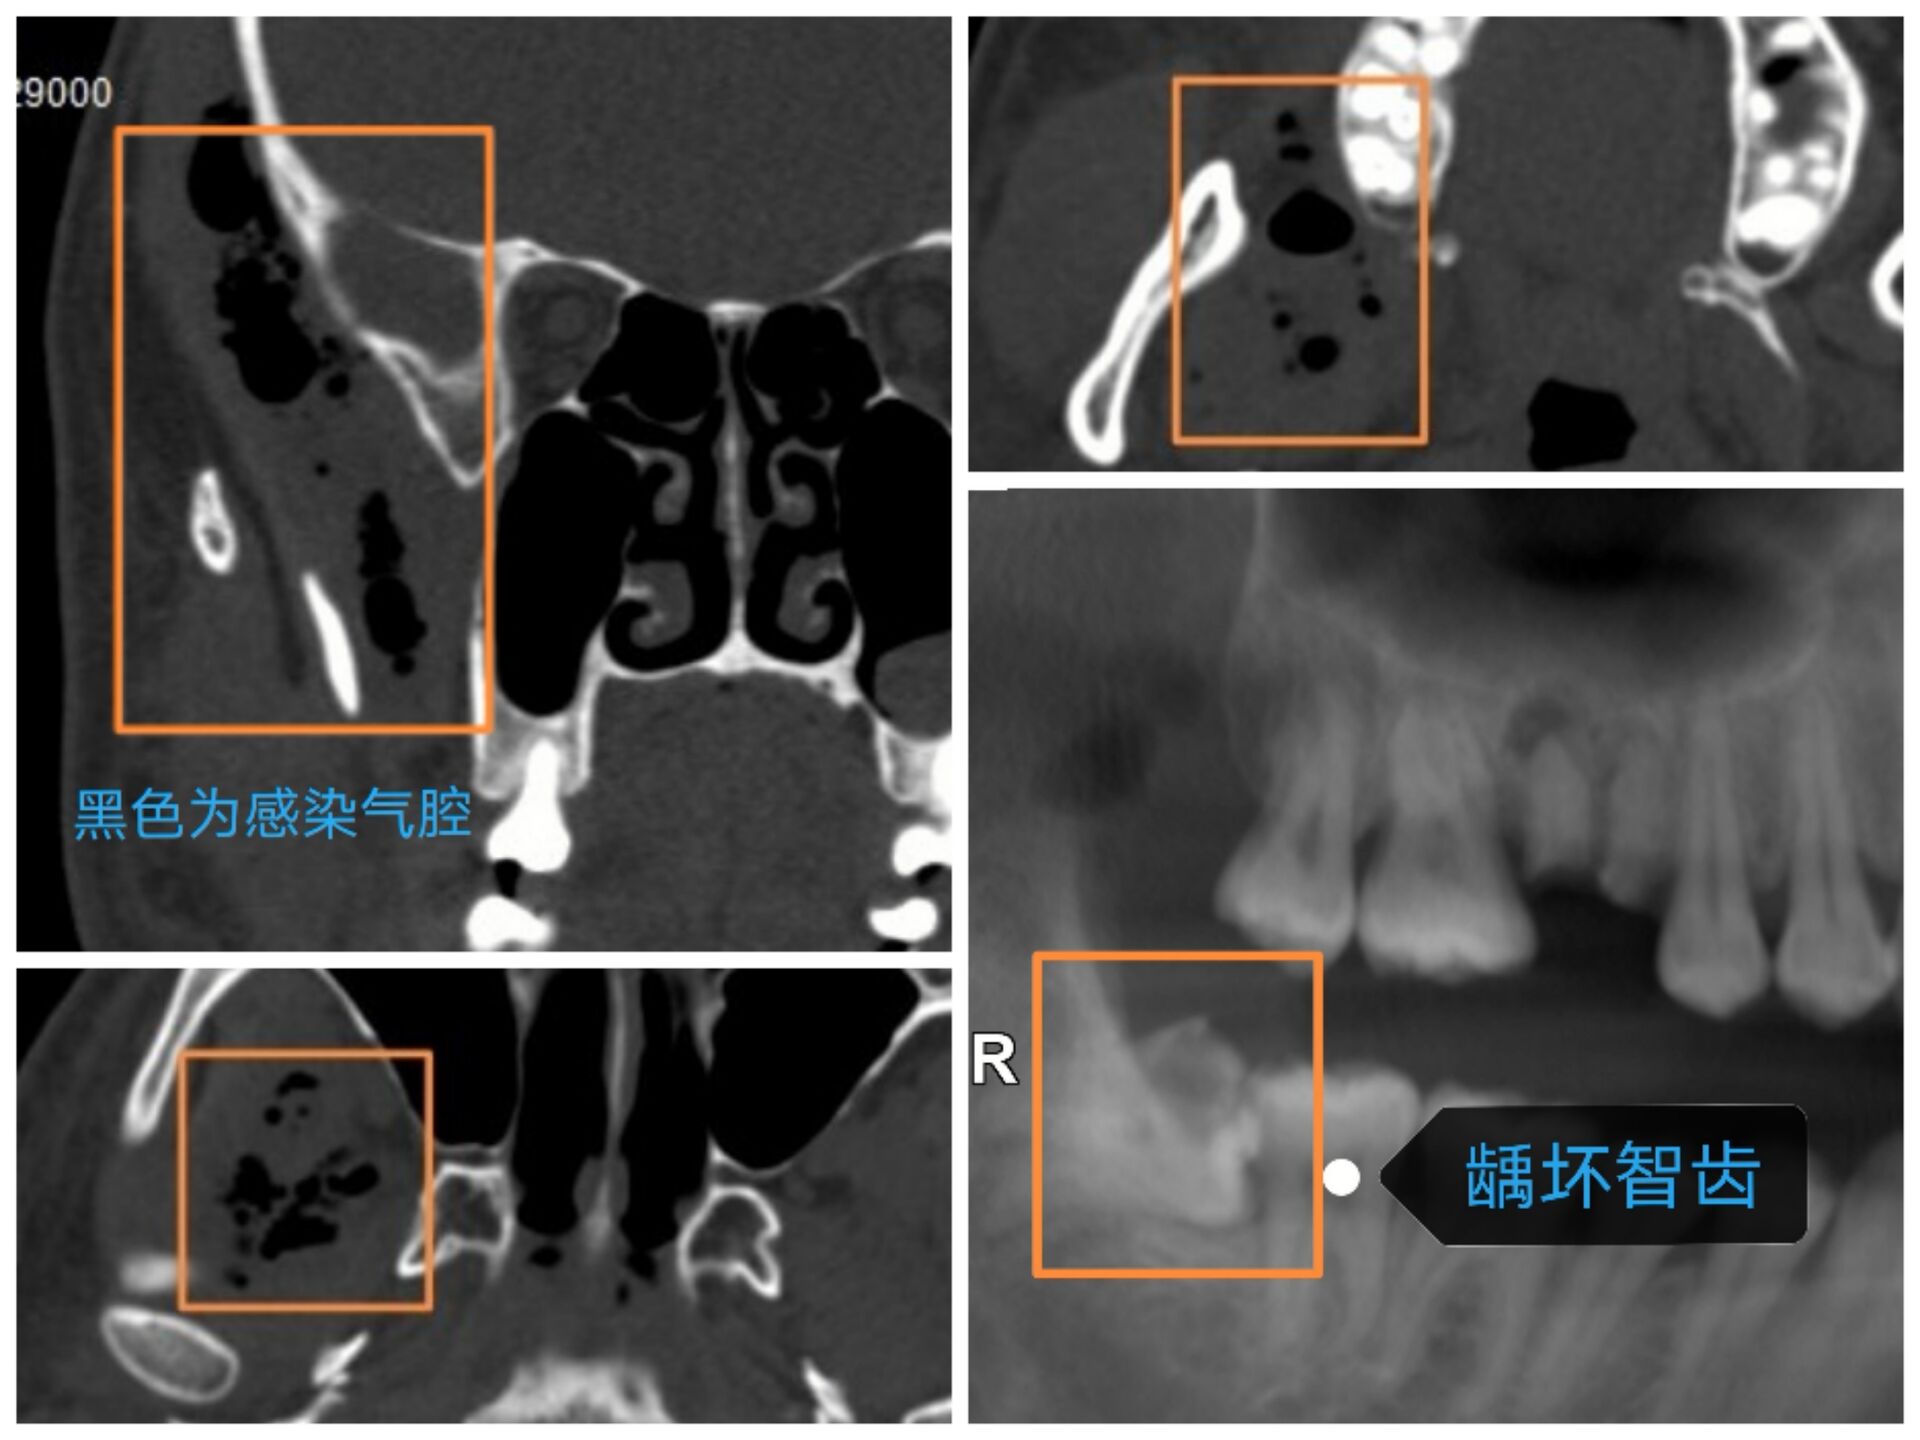

智齿容易引起感染,损害健康,甚至危及生命。如,一,冠周牙龈软组织引起的发炎。智齿萌出不全,部分牙龈覆盖,容易积存食物导致局部牙龈肿痛、化脓。这种情况尚属轻症,通过局部处理,口服抗生素即可恢复。冠周炎若治疗不及时,也有小部分会发展成邻间隙感染,此时症状严重,伴有发热、乏力等全身症状,只有通过手术才能治愈;二,龋坏智齿。细菌通过根管内牙髓组织,到达根尖区颌骨,引起感染。智齿牙根一般都比较深,尤其是牙根尖,感染继续扩散的话,就会造成颌面多间隙的感染,损害健康,危及生命。

病历二